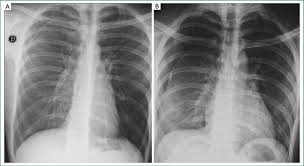

The lungs can be seen to reach the inner edge of the thoracic wall (arrows). Tap on/off image to show/hide findings. Schematic illustration of the radiographic findings and differences between pneumothorax and artifacts related to skinfolds. An occult pneumothorax refers to one missed on initial imaging, usually a supine /semierect chest radiograph 24. This is the one not to miss.

Ultrasound imaging also may be used to identify a pneumothorax. Many observations suggest that spontaneous pneumothorax often results from rupture of a subpleural bleb. Patients with tension pneumothorax usually appear dyspnic and distressed. All patients suspected of having pneumothorax; Pneumothoraces may be small or very large. Tap on/off image to show/hide findings. Pneumothoraces) means the presence of gas (usually air) in the pleural space. If a hemothorax occurs concurrently with a pneumothorax it is then termed a hemopneumothorax. This is the one not to miss. Tap on/off image to show/hide findings. Tap on/off image to show/hide findings. The lungs can be seen to reach the inner edge of the thoracic wall (arrows). Distracting injuries such as fractures or peritonitis were also noted.

Patients with a larger pneumothorax may have decreased movement of the chest wall, a positive coin test result, diminished fremitus, or decreased to absent breath sounds on the affected side. Most individuals with primary spontaneous pneumothorax (psp) have unrecognized lung disease; If a hemothorax occurs concurrently with a pneumothorax it is then termed a hemopneumothorax. The video is an effort to revisit the pneumothorax. Radiographic findings of 2.5 cm air space are equivalent to a 30% pneumothorax. Please see disclaimer on my website www.academyofprofessionals.com Ipsilateral pleural line with reduc ed/absent lung markings (i.e., increased transparency) abrupt change in radiolucency; Schematic illustration of the radiographic findings and differences between pneumothorax and artifacts related to skinfolds. 6 10 supportive findings of pneumothorax. Distracting injuries such as fractures or peritonitis were also noted. Tap on/off image to show/hide findings. Clinical signs of a tension pneumothorax in the ventilated patient are comparably rapid, with arterial and mixed venous peripheral capillary oxygen saturation immediately decreasing 5. A pneumothorax refers to the presence of gas or air in the pleural space.